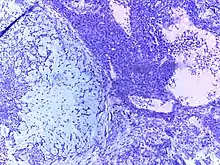

![]() | Lymphocyte | Micrograph showing lymphocytes in caseating granuloma. | Category: Lymphocytes | Lymphocyte |